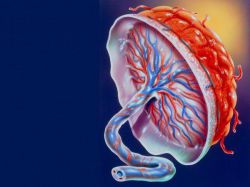

Защелачивание организма, или алкалоз, имеет множество причин, и его механизмы развития могут быть как внутриклеточными, так и системными. Известно несколько видов алкалозов: газовый, метаболический, выделительный, экзогенный и смешанный.